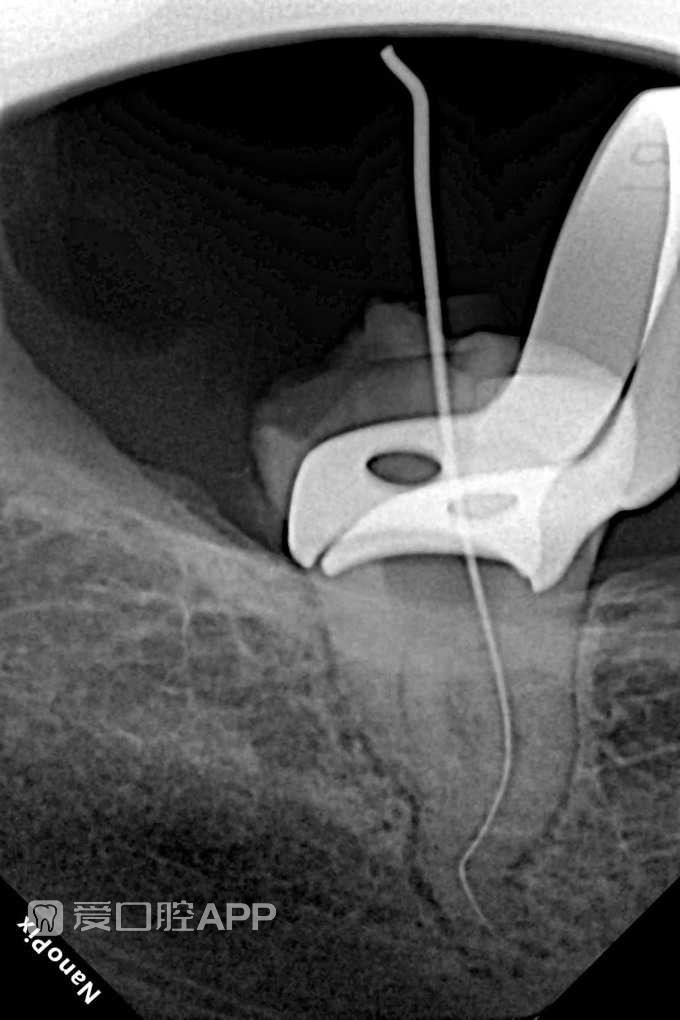

看个根充:下8 by Muhannad Takruri